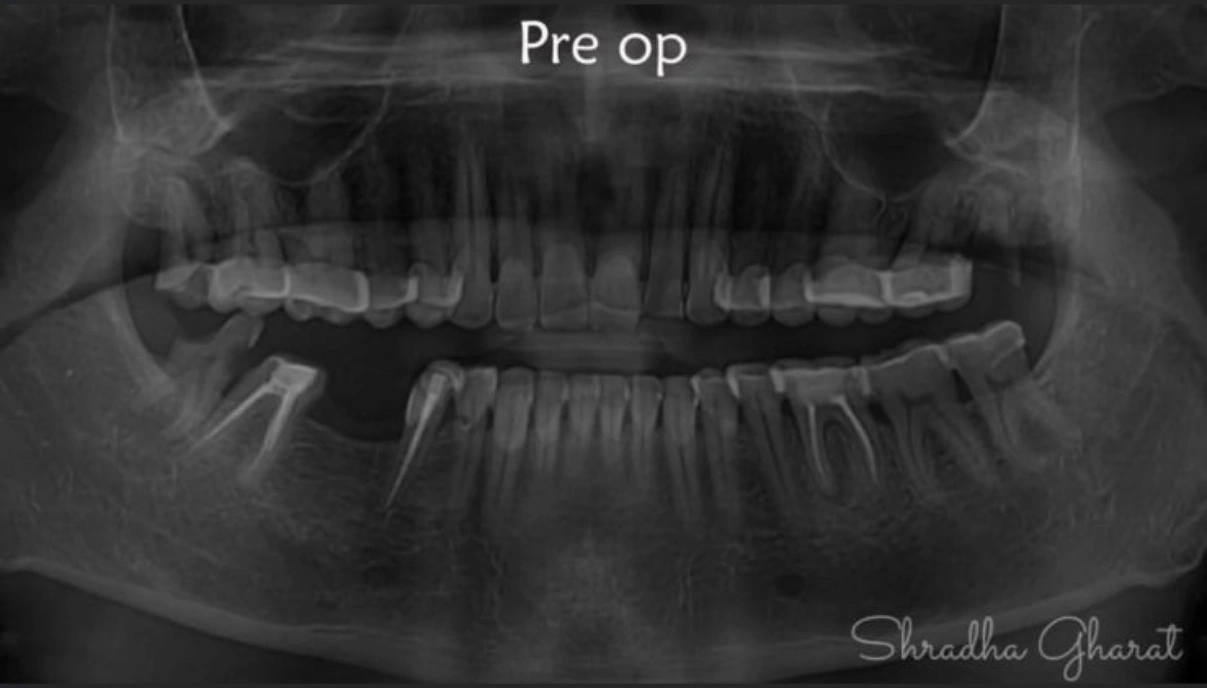

Full mouth rehabilitation includes restoration of lost tooth structure and bite. This technique sensitive procedure involves buildup of lost tooth enamel and dentin. Missing tooth can be replaced with Dental Implants or dental bridges. A Full mouth Reconstruction procedure is mainly indicated for patients with extreme tooth wear.

Full mouth rehabilitation (FMR) is a treatment plan for restoring function and function tolerance of dentition after surgery or dental restoration. It aims to restore dentition to the optimal point of function and esthetics of a healthy mouth. The treatment plan provides patients with a permanent smile that looks natural and bright.

Multiple dental treatments join hands to give you something more than a mere smile makeover. Based on the case history of patient and nature of defects, the following can be advised:-